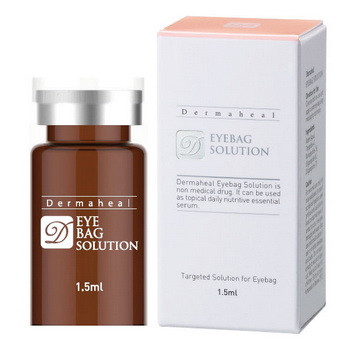

Филлеры гиалуроновой кислоты

Филлеры – препараты, которые способны заменить дорогостоящие и травматические пластические операции. Они на основе гиалуроновой кислоты наполняют пустоты в толще кожи – морщины, рубцы. Гиалуриновая кислота является веществом, совместимым с составом межклеточной жидкости дермы.

Филлеры гиалуроновой кислоты направлены на действие в определенных зонах:

- Морщинки в уголках глаз;

- Складки в уголках губ;

- Межбровные морщинки;

- Носогубные складки;

- Рубцы;

- Подтягивание контурного овала лица;

- Наполнение скул, подбородка, щек;

- Подтягивание кожи кистей рук.